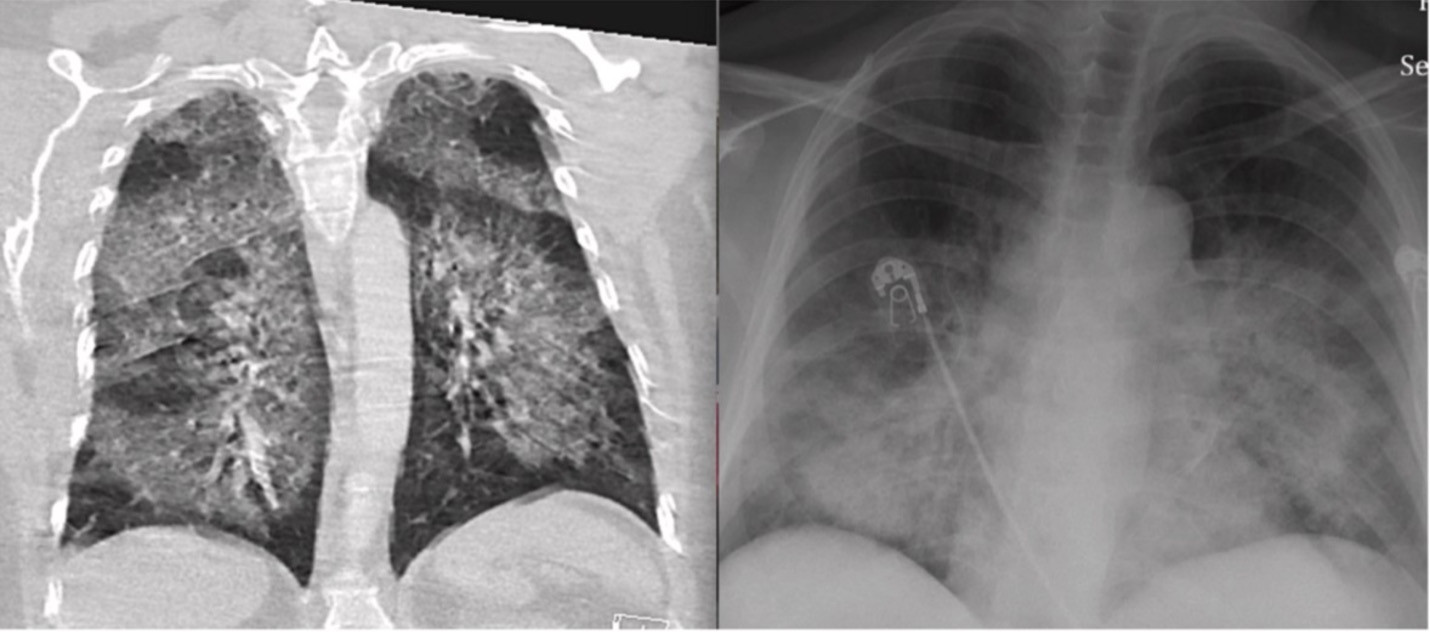

Thứ nhất, thuốc lá điện tử gây tổn thương nhu mô phổi. Hình ảnh kính mờ lan tỏa nền phổi 2 bên, là biểu hiện kinh điển trong bệnh lý này. Các tác nhân có trong thuốc lá điện tử tác động trực tiếp lên phổi, gây ra tổn thương phổi cấp tính đã được ghi nhận là hình ảnh phổ biến nhất trong mô bệnh học.

Đặc biệt, thuốc lá điện tử còn là liên quan một đợt bùng phát bệnh lý mới ở Mỹ khiến nhiều người bị tổn thương phổi. Căn bệnh này được gọi là EVALI (tổn thương phổi cấp liên quan thuốc lá điện tử). Dịch bùng phát mạnh vào tháng 8/2019 và đạt đỉnh vào tháng 9/2019. Tới 18/2/2020, 2807 ca mắc căn bệnh này trên toàn nước Mỹ, 68 ca tử vong được khẳng định có liên quan.

Triệu chứng của bệnh là khó thở, ho, đau ngực, tiêu chảy, đau bụng, sốt, mệt, xuất hiện hàng giờ, hàng tuần trước khi nhập viện, đồng thời, máu lắng tăng, CRP tăng, bach cầu tăng, GOT/GPT tăng, phim chụp X-quang cho thấy có tổn thương phổi.